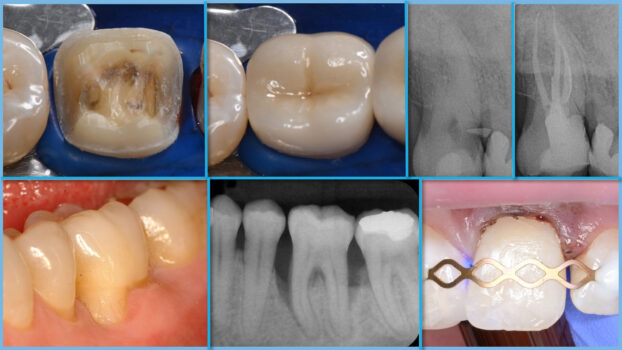

The postgraduate course in „Dental Conservation“ is aimed at dentists who wish to continue their education in a structured and in-depth manner in the various areas of dental conservation and graduate with the „M. Sc.“ certificate, which is a mark of quality for the practice. Dental conservation plays an important role in routine dental practice. The subjects covered in depth are „Restorative Dental Conservation“, „Periodontology“, „Endodontology“ and „Preventive and Pediatric Dentistry“. Dentists with a German license to practice medicine and at least 1 year of professional experience can apply. The course can also be studied part-time.

In the first four semesters, the subjects of dental conservation are taught: restorative dental conservation, periodontology, endodontics, preventive and pediatric dentistry. The Master’s thesis follows in the fifth semester. During the semester, lectures and clinical case discussions are held every week in a hybrid format. The main focus is on patient treatment, which is carried out in the student’s own practice. A specified treatment catalog is to be fulfilled in each of the four subjects. The cases are documented according to the prescribed form and discussed in the case discussions. There are 2-3 hands-on courses per semester on Friday afternoons, the dates of which are set in advance.

restorative dental conservation, periodontology, endodontics, preventive and pediatric dentistry